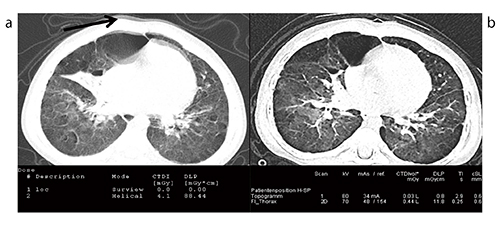

Case12は他院で鎮静を行ってCT撮影をした小児の例であるが,鎮静をしても体動アーチファクトが見られるのに対し(図19 a),数か月後にSOMATOM Forceにて行った鎮静なしのハイピッチ撮影では体動アーチファクトは見られず(図19 b),DLPも約88 mGy・cmから約12 mGy・cmに低減している。

図19 Case12:低線量でのSedation Free CT〔従来CT(a)との比較〕

(70kV,DLP 11.8mGy・cm)